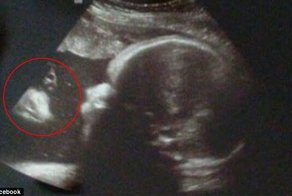

- Пара "видит Иисуса" на УЗИ-снимке своего ребенка